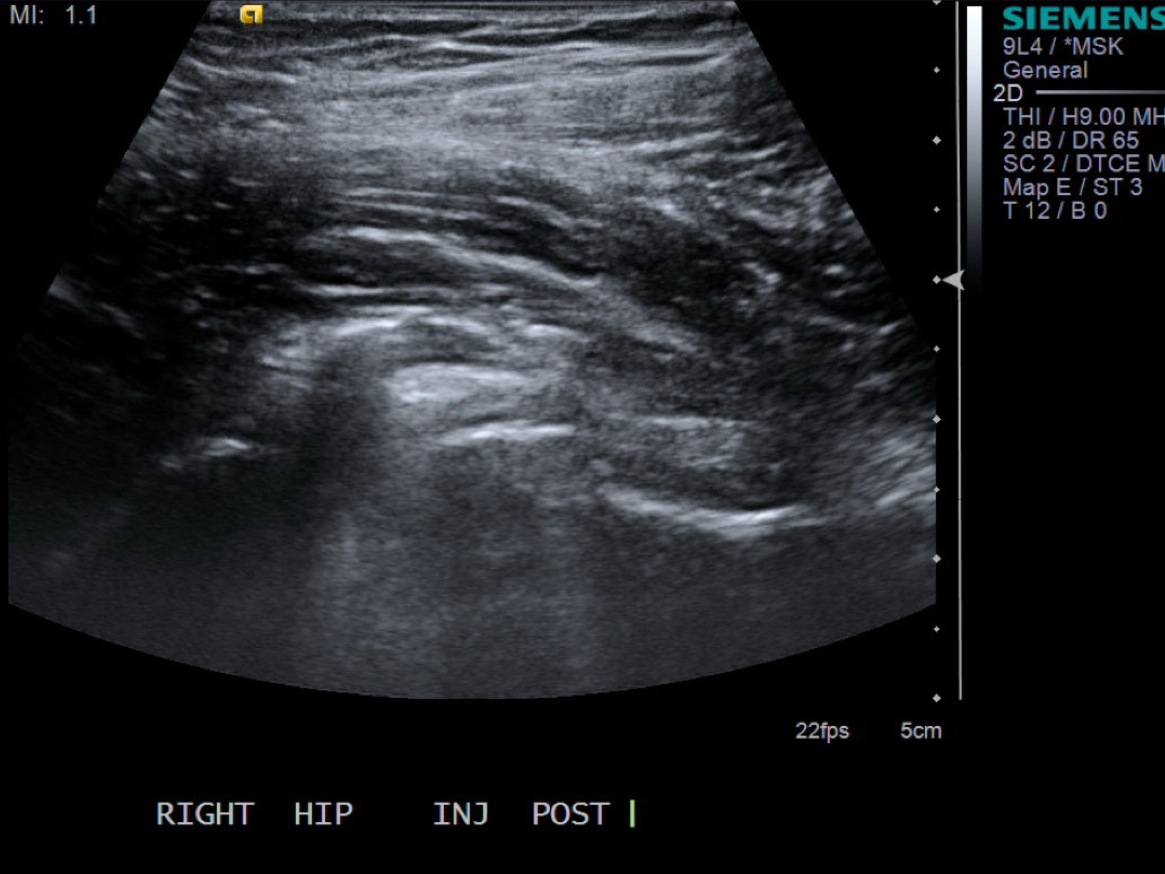

12. Scan joint to demonstrate distention. Can try to flex hip to see if fluid distended.

• descriptiondescription